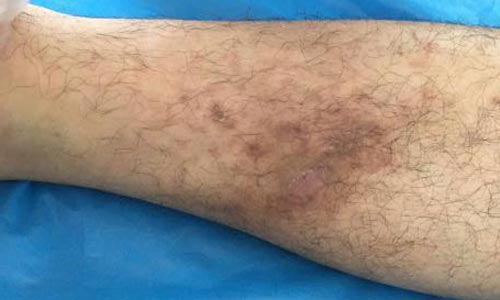

(图:治疗前,患者右腿关节病灶)